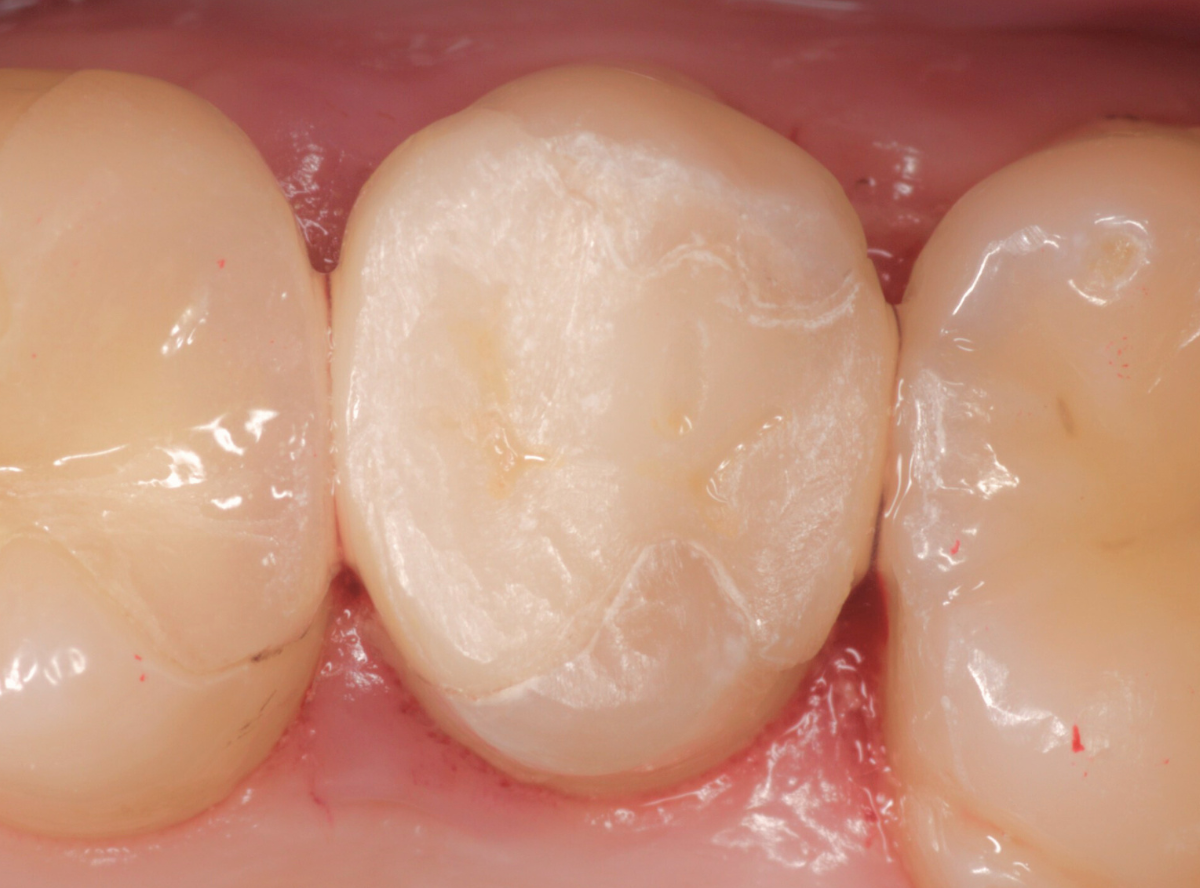

治療後の状態です。

自然な仕上がりで、患者さんにもご満足いただけました。